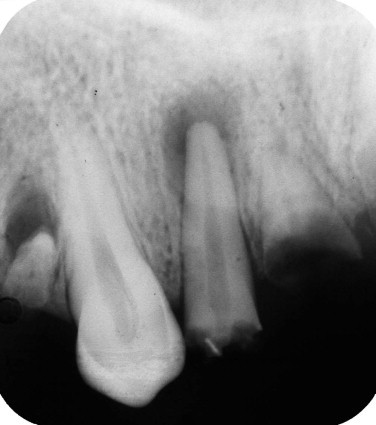

What is this?

Nasopalatine duct cyst

What is this radiolucency?

What is the raised area on anterior palate?

(it also involves bone)

What is this if not a nasopalatine duct cyst?

Median palatal cyst

What is this if teeth are vital and it doesn’t involve bone?

Cyst of the incisive papilla